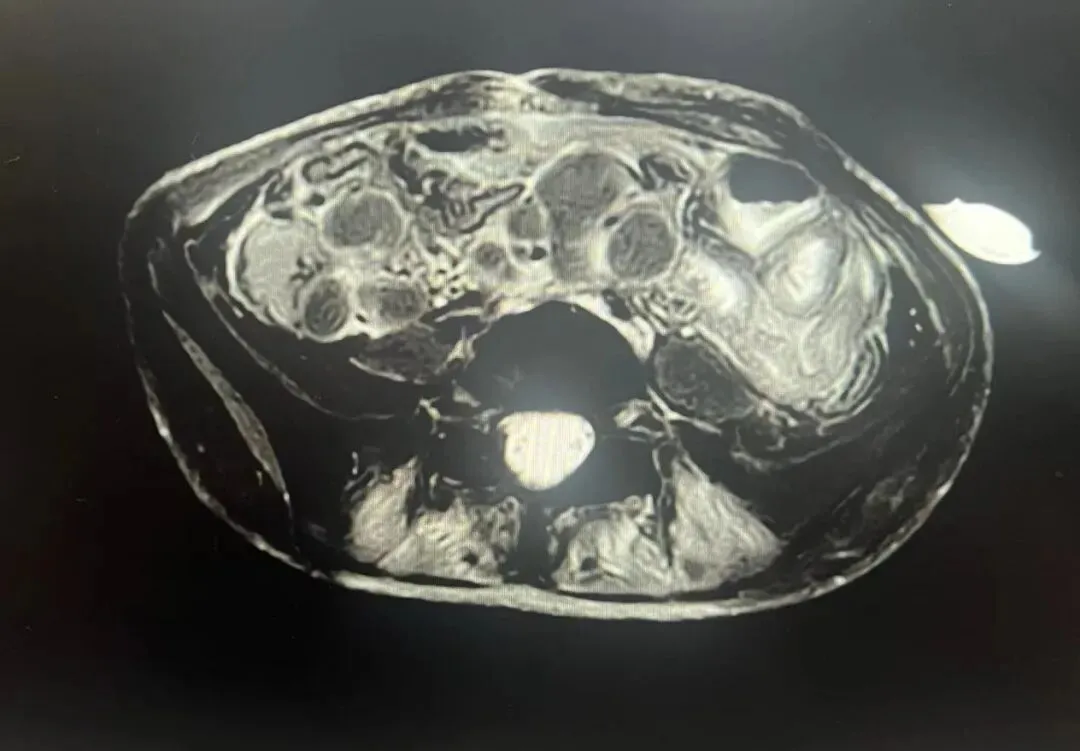

腹腔淋巴结

主刀的普外科副主任章跃滨通过腹腔镜进入腹腔后,不禁倒吸一口凉气:腹腔内布满黄绿色脓液和干酪样物质,肠道周围的淋巴结肿得像鸡蛋一般,2米长的肠子近一半糜烂受损,其中30厘米严重糜烂并完全穿孔。为控制感染、保住小月的生命,医生紧急转为实施开腹手术,切除坏死回肠并做肠造瘘处理。

术后的全面检查,最终证实了小月的病因——结核感染。胸部CT显示,她的双肺布满白块,还伴有多个坏死空洞。感染科主任黄丽素推测,结核菌最初潜伏在小月肺部引发反复咳嗽,随后通过血液和淋巴系统全身扩散,在腹腔淋巴结“扎根”后攻击肠道,进展为肠坏死、肠穿孔,若送诊再晚一步,肠道穿孔引发的一系列休克、多脏器功能衰竭,可能就直接夺走了孩子的生命。